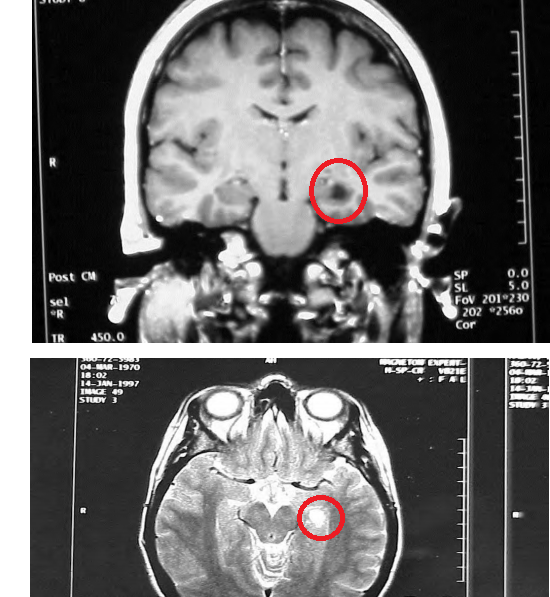

28 YOA FEMALE

Limbic seizures may include an aura of smell, an epigastric rising sensation, feeling of fear, and memory loss (such that pt is unaware/does not remember that they had a seizure).

Epilepsy: especially complex partial seizures: limbic seizures may include an aura of smell (from the uncus) or an epigastric rising sensation (from the insula), or may include fear (suggesting activation of the amygdala) as a primary manifestation. Memory loss occurs following limbic seizures that involve the hippocampus, such that a patient may not know (remember) that he/she had a seizure